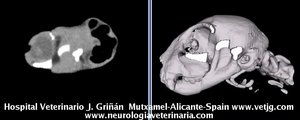

Mismo paciente: Correspondencias entre el corte sagital y el volumen, ambos reconstruidos a partir de imágenes TC (transversales) |